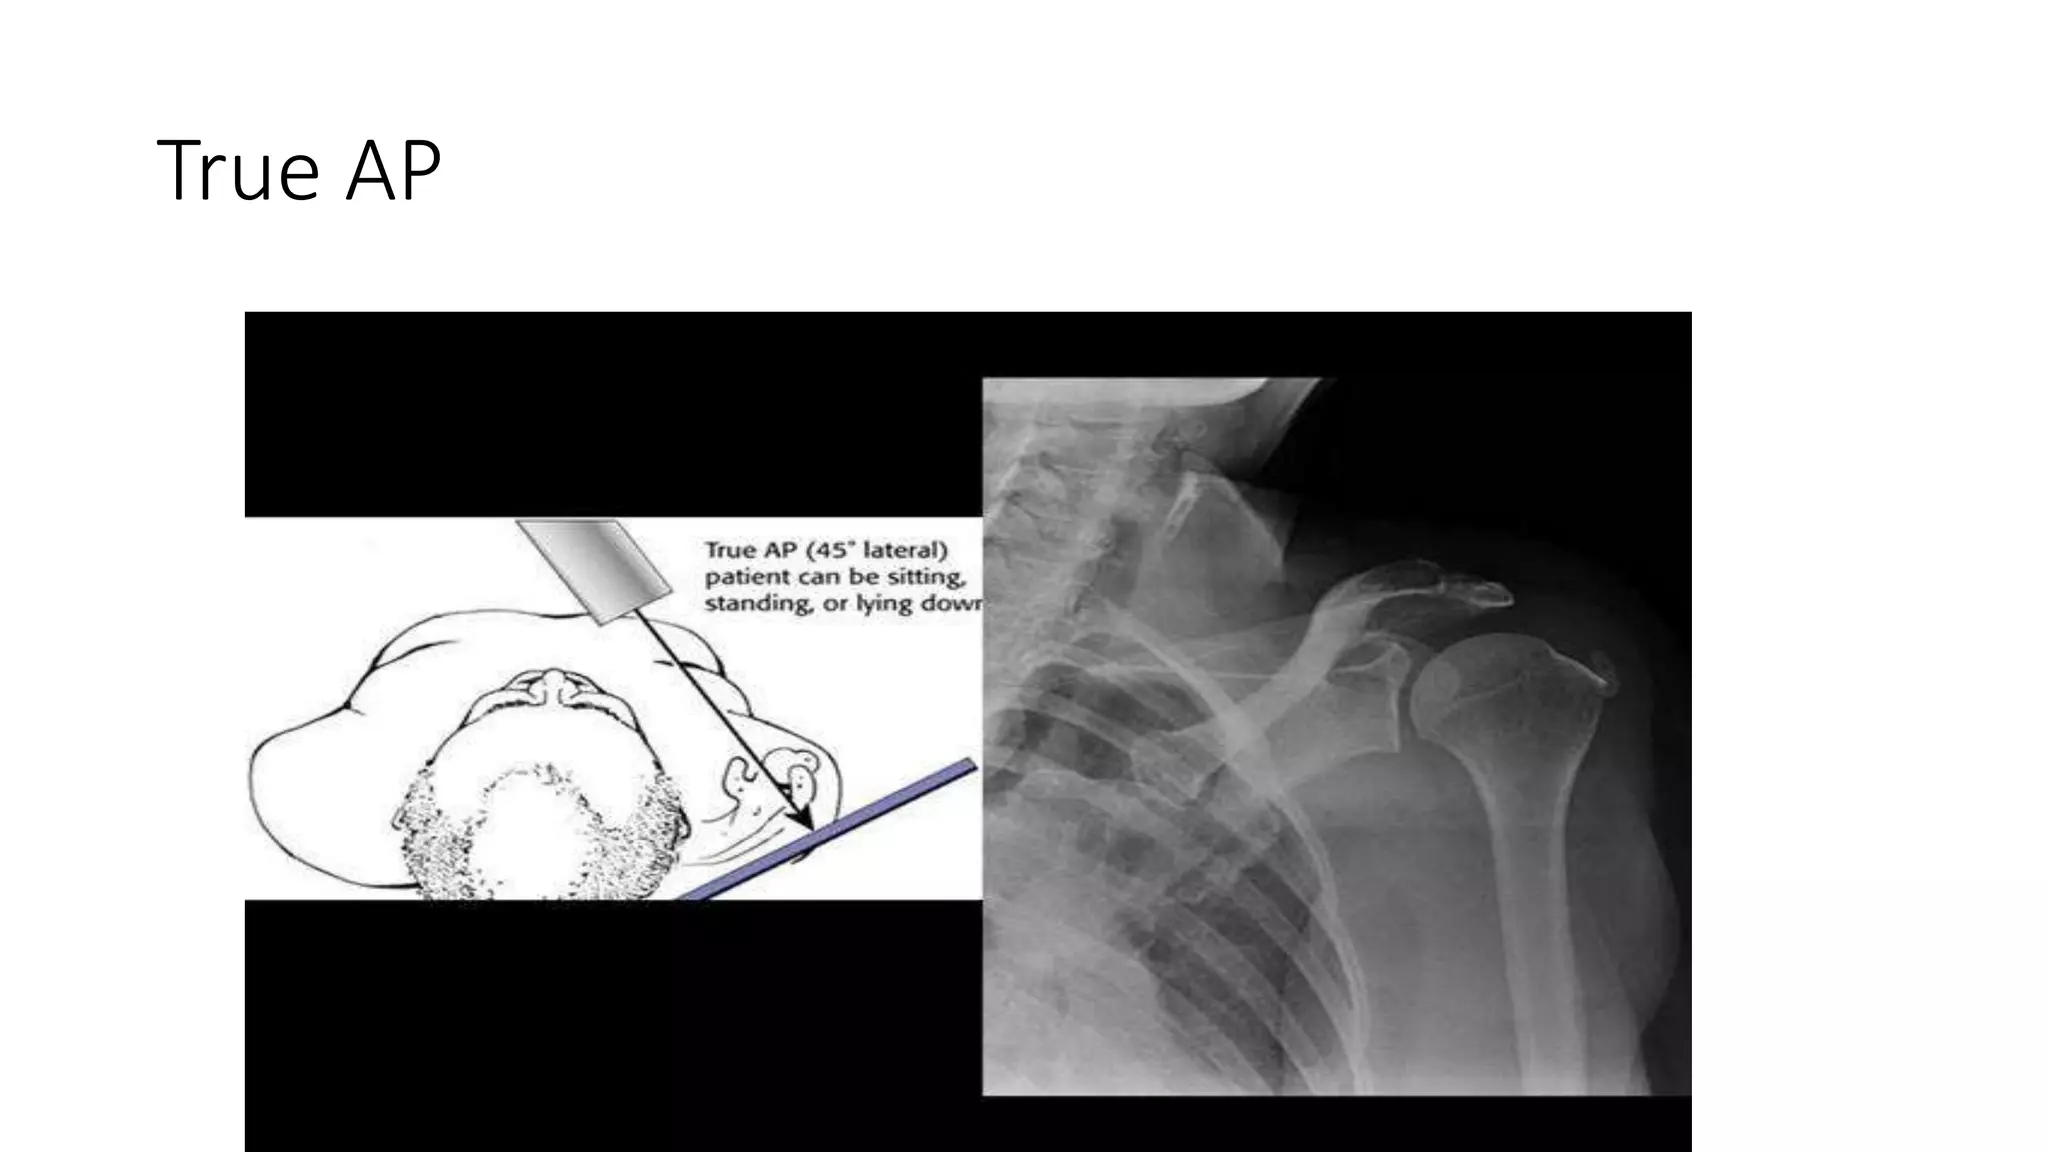

True AP

Imaging Radiographs • true AP •scapular Y • axillary other helpful views • West Point view :- shows glenoid bone loss • Stryker view :- shows Hill-Sachs lesion • CT scan • helpful for evaluation of bony injuries • MRI • best for visualization of labral tear • addition of intraarticular contrast • increases sensitivity and specificity